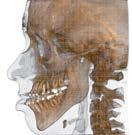

L’innovazione e la sicurezza sono due dei valori perseguiti dallo Studio Braconi a Terni, un punto di riferimento nell’ambito della radiologia 3D ortopedica grazie alla presenza del macchinario Newton 5G XL: si tratta dell’unico apparecchio nel Centro Italia che permette di eseguire una perfetta diagnostica per immagini in ortopedia e per la cervicale, oltre per le piccole articolazioni come seni paranasali, orecchie, colonna cervicale, gomito, polso, mano, ginocchio, caviglia e piede.

Nell’ambito della radiologia 3D ortopedica, il centro diagnostico utilizza il nuovissimo macchinario NewTom 5G XL, in grado di individuare con la massima precisione la presenza di fratture o lussazioni delle articolazioni, controllare la corretta guarigione di una frattura, valutare una lesione o una ferita causata da infezione, artrite o crescita anormale dell’osso.

Il tutto mediante una semplice e veloce scansione, grazie alla quale si otterranno diverse immagini in 3D ad altissima risoluzione e, per ottenere immagini ancora più nitide mediante un bassissimo dosaggio di radiazioni, gli esperti si avvalgono dell’innovazione racchiusa nella tecnologia Cone Beam.